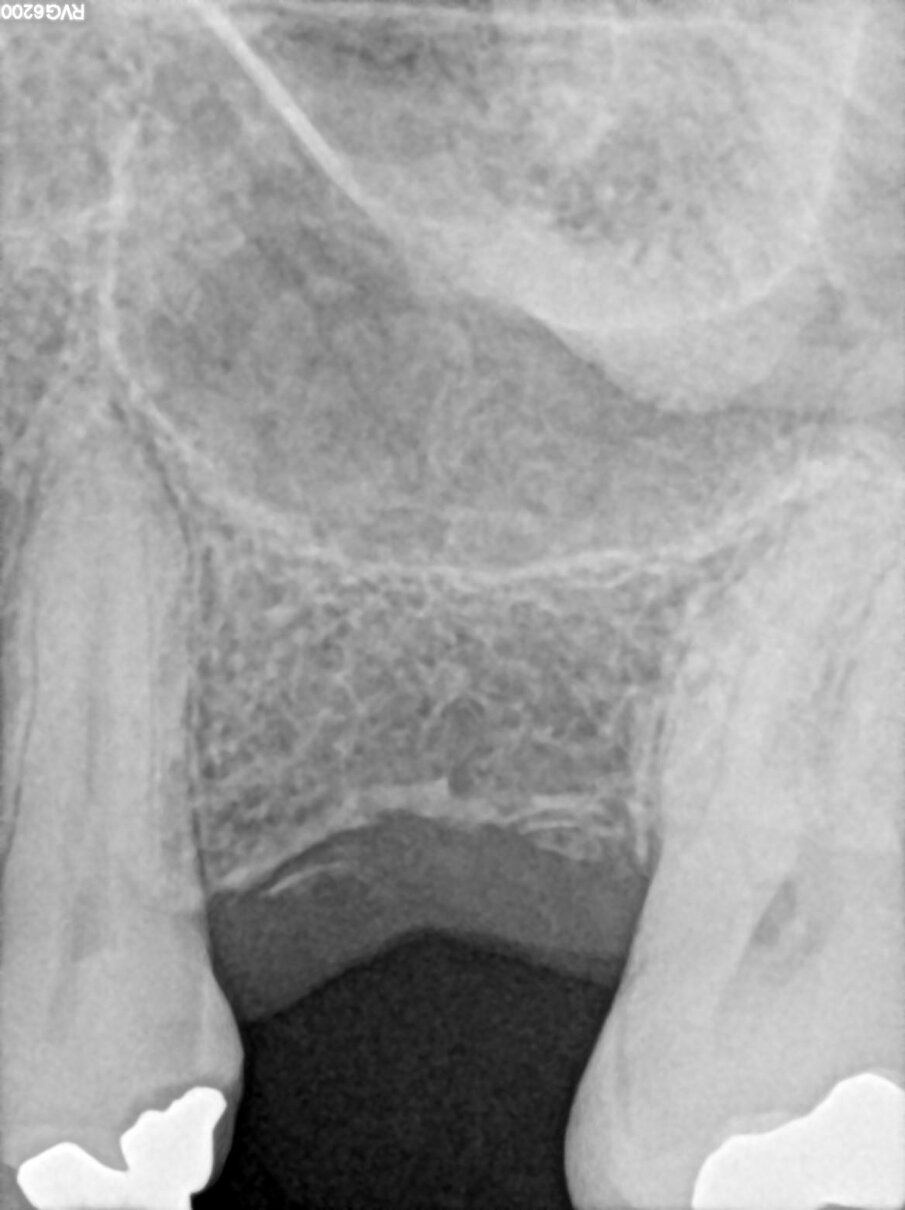

Le radiografie a tre mesi hanno evidenziato un buon rimaneggiamento del biomateriale e segni di neoformazione ossea dal pavimento del seno, confermando le proprietà osteogeniche di OsteoBiol Putty. A sei mesi, l’osso innestato risultava completamente rigenerato, permettendo la finalizzazione protesica con una corona in disilicato di litio cementata su cappa in titanio (Figg. 6-13).

Fig. 6_Radiografia post-operatoria.

Fig. 7_Follow-up radiografico a 3 mesi.